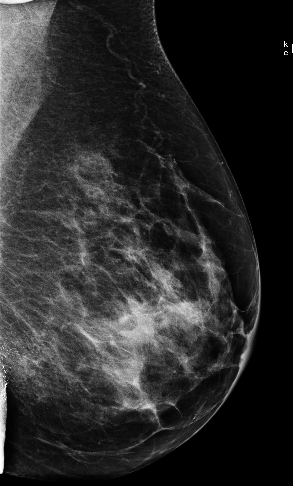

Masking refers to the phenomenon in which a tumor is hidden by the surrounding breast tissue, causing the cancer to be difficult or even impossible to discern with regular mammography, as seen in Figure 2. Masking can also result in large invasive cancers111We define large invasive cancers as those confirmed to have spread and be 2cm at time of diagnosis. – a small cancer may be difficult to discern in certain images, allowing it to grow to a more lethal size. Masking is correlated with breast density, as it has been shown that cancer in dense breasts is more likely to be missed during screening [5, 6, 7]. Density can be subjectively assessed by radiologists via the BI-RADS density standard (ACR) [8, 9], or measured by automated tools such as Libra [10]. These density measurements, however, do not perfectly correlate with masking potential. Radiologists consider the distribution and pattern of tissue when assessing masking potential, and have called for automated methods to assess the masking effect [11]. Until now, the question of exactly how masking potential should be quantified remains an open one, although some subjective notion has been added to certain categories of the most recent edition of BI-RADS density [12].

In this work, we introduce the CSAW-M dataset – a collection of over 10,000 mammographic images and associated masking assessments from experts. The assessments were graded by radiologists according to 8 levels of masking potential, as depicted in Figure 1, from easily assessed mammograms with low-masking potential (level 1) to difficult-to-assess examples with high-masking potential (level 8). This data can be used to train models capable of predicting masking potential from mammographic images in an ordinal classification setting.

The goal of the annotation procedure was to label each image with expert assessments of masking potential. Masking was quantized into 8 bins, or levels, as depicted in Figure 1, for the public training and test sets. Images in the private test set are fully sorted according to masking. Individually sorted examples provide a more granular assessment, but at the cost of increased annotation time. We opted for fine granularity on the private test set because (1) it allows for a more fine-grained assessment, and (2) it allowed us to identify robust initial bins555We use “bin” and “level” interchangeably to denote collections of images with similar masking potential. for the 8 masking levels in the public training/test sets. To represent the initial bins, we chose images personalized to each radiologist, but with highest agreement among the other experts. The benefit to this approach is that the starting point respects subjective assessments while at the same time choosing representative examples for each masking level.

We begin by considering the question how well do the experts agree w.r.t. masking potential? This is an important question to consider, as the main task is to emulate the median expert assessment. Table 3 shows experts have an AMAE ranging from 0.68 to 1.04. This suggests that, on average, individual experts are almost masking levels distant from the ground truth – a reasonable level of agreement. A more nuanced picture of expert agreement is given in Figure 5. Here, agreement between each expert, as well as the ground truth, is measured by Kendall’s . As a rule-of-thumb Kendall’s 0.3 indicates a strong association 666We refer the reader here for an interpretation of Kendall’s .. According to this rule, all experts have a strong association, although we can see that experts 1, 2, and 5 exhibit substantially higher agreement than experts 3 and 4. Interestingly, the experts who tended to agree more were also less experienced. Turning to the F1-scores in Table 3, it is clear that experts are in better agreement for low-masking cases than for high-masking cases. This suggests that high-masking potential is a generally less agreeable property than low-masking potential. Our findings on the public test set are mirrored in the private test set, provided in Appendix F. Examples of mammograms where experts agree and disagree are provided in Figure 4.

The models seem to be more correlated with Experts 1, 2, and 5, who agreed with each other more often (and the ground truth). Interestingly, our models were more correlated with each individual radiologist than any of their colleagues were (see the two rightmost columns in Figure 5). Please note that the cross-tabulation in Figure 5b is asymmetric because the number of mammograms placed into each masking level is different for each radiologist – i.e. the AMAE between two experts changes depending on which one is considered as the reference. In Figure 4, we provide several examples where the networks both agree and disagree with the experts. Figure 4(g) is an interesting case because the density is fairly low but experts rate it as high masking potential. Our models under-estimate the masking, suggesting they rely too heavily on general density cues.